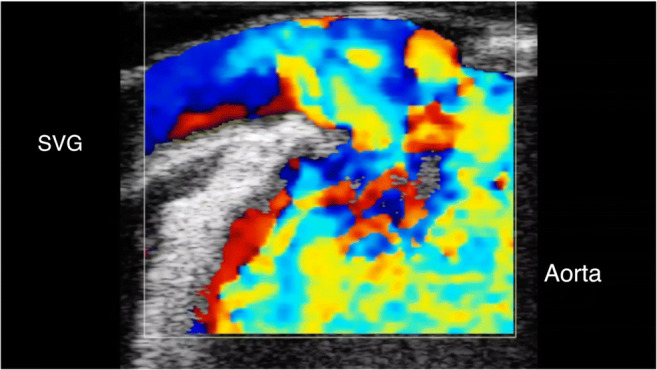

In off-pump procedure, the scan of the anastomosis should be done during stabilization of the vessel to avoid motion artifacts and obtain good quality imaging. In on-pump CABG, for free-graft, the scan should be performed by gently injecting the conduit with blood. The proximal anastomosis itself should be scanned (Fig. 3). In case of arterial conduit, the temporary opening of the graft permits to obtain adequate imaging. The anastomosis should be checked in both long- and cross-sectional views with 2-D and color flow mapping (Fig. 4). To obtain good acoustic coupling, a sterile gel can be used or the pericardium can be filled with saline solution. For TTFM, the flow meter should be connected to patient’s EKG and blood pressure in order to obtain reliable measurements, especially for the parameter DF. The measurement is obtained after the completion of anastomosis with the heart in normal position in off-pump surgery, after aortic cross-clamp release in on-pump surgery and weaning from cardiopulmonary bypass. The last measurement should be done after heparin reversal before chest closure either in off- or on-pump CABG. The technical aspects to obtain reliable TTFM measurements are related to avoid any compression of the graft with a too small a probe (use probe with adequate caliber), obtain good acoustic coupling using the gel, measure as close as possible to the anastomosis, and avoid vessel kinking.

Fig. 3.

Proximal anastomosis of a saphenous vein graft to the aorta